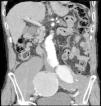

Paciente varón de 86 años, hipertenso en tratamiento con 2 fármacos, con historia de dolor lumbar con irradiación crural derecha de varios meses de evolución que se había controlado parcialmente con tratamiento sintomático. Su reumatólogo le había prescrito RM dorsolumbar que no llegó a realizarse ya que el paciente acudió antes a urgencias por aumento de la intensidad del dolor. En la analítica, hemoglobina 8,4g/dl, LDH 318 U/l, creatinina 1,29mg/dl, PCR 6,16mg/dl, VSG 24mm/h y leve hipoproteinemia. Ausencia de signos de inestabilidad hemodinámica. Se realizó una TC abdominopélvica con contraste por vía intravenosa que muestra aneurismas ilíacos aislados bilaterales>6cm (fig. 1) con rotura contenida del derecho (fig. 2), que desplazaba el músculo psoas (fig. 3) y horadaba el hueso ilíaco ipsolateral (fig. 4). El paciente es sometido a by-pass aortobifemoral pero lamentablemente fallece en el postoperatorio.

Los aneurismas ilíacos aislados, sin aneurisma aórtico asociado, son raros1. Son relativamente difíciles de identificar, ya que hasta un 40% de ellos se pueden presentar con rotura2. La tasa de incidencia de causas extraespinales de ciática es baja3. Igualmente, el aneurisma roto crónico constituye una entidad peculiar. Todas estas circunstancias se aúnan para que el diagnóstico, la mayoría de las veces, sea erróneo y tardío4. Suele tratarse de una rotura laterodorsal hacia las inserciones anteriores del psoas que contiene el hematoma, evitando la extravasación masiva pero no la infiltración de las raíces del plexo lumbosacro, lo que origina un dolor crónico lumbar con irradiación al miembro inferior5, siendo esta su presentación más frecuente6. El diagnóstico puede realizarse con TC abdominal7, pudiendo también visualizarse en la RM lumbar (corte parasagital)7,8. En cualquier momento de la evolución, el aneurisma puede sufrir una rotura aguda secundaria4. Este caso sirve para recordarnos, en nuestra práctica diaria, que la causa aneurismática puede estar implicada en los síntomas de ciática9.